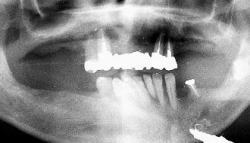

| 治療前 | 治療後 |

| 上顎、下顎共にグラツキの著しい歯は抜歯し、上顎はAll-on-4、下顎奥歯は通常のインプラントブリッジとしました。 | |